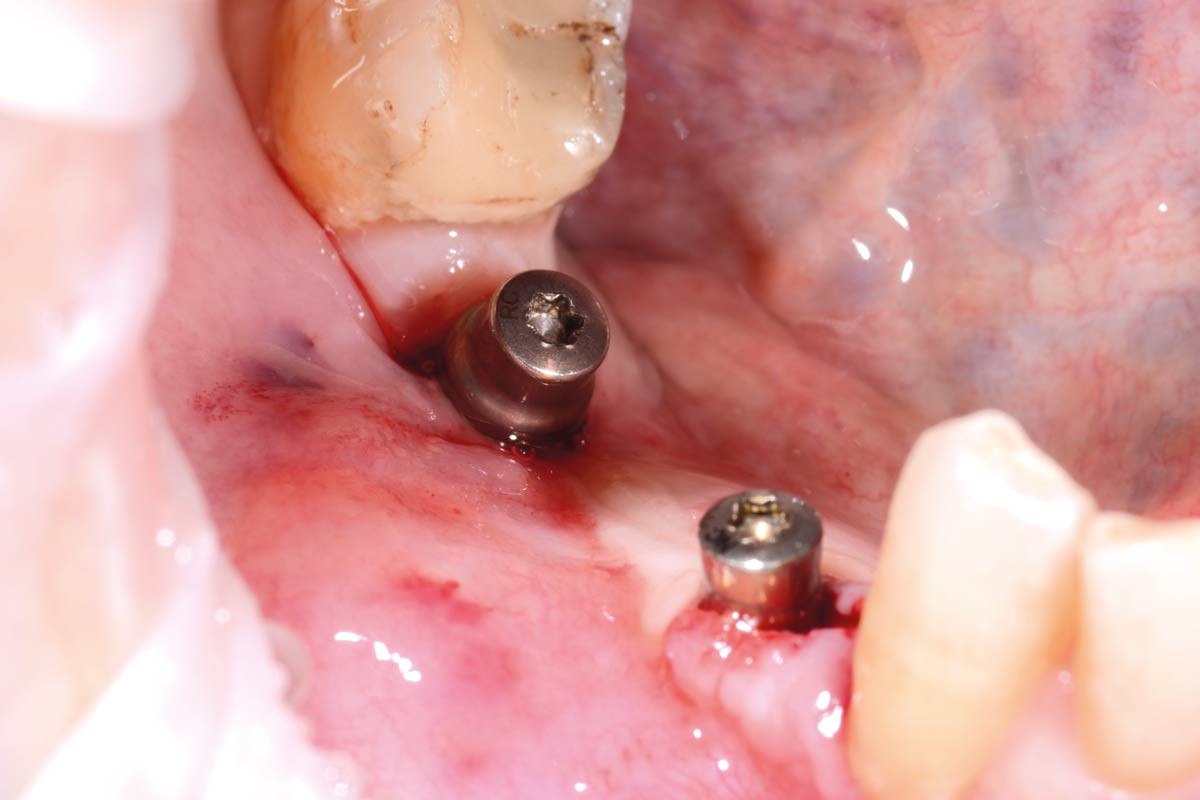

18/29 - Insertion of 2 Straumann BLT implants (regio 4.4: 3.3 x 10 mm, regio 4.6: 4.1x 8 mm), excellent primary stabilityVertical bone augmentation and broadening of attached gingiva using cerabone®, permamem® and mucoderm® - Dr. R. Naimoli